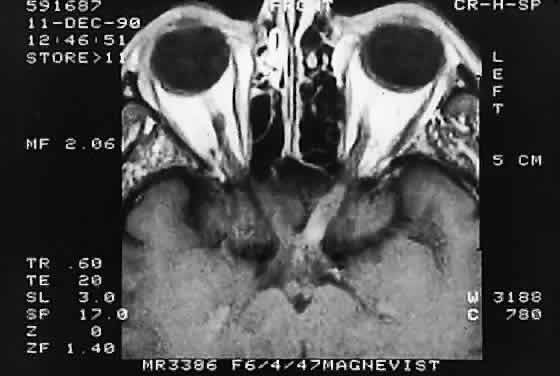

The optic nerve is affected in some manner in 1% to 5% of patients with sarcoidosis and is the second most frequently involved cranial nerve—the facial nerve being the most common.67,68 Rarely, sarcoidosis may present as tumefactive enlargement of the optic nerve without evidence of systemic disease. Most cases are misdiagnosed initially as meningioma or orbital pseudotumor (Figs. 50 and 51).67,69

Fig. 50. Bilateral thickening of the optic nerve and sheaths due to sarcoidosis. Computed tomography.